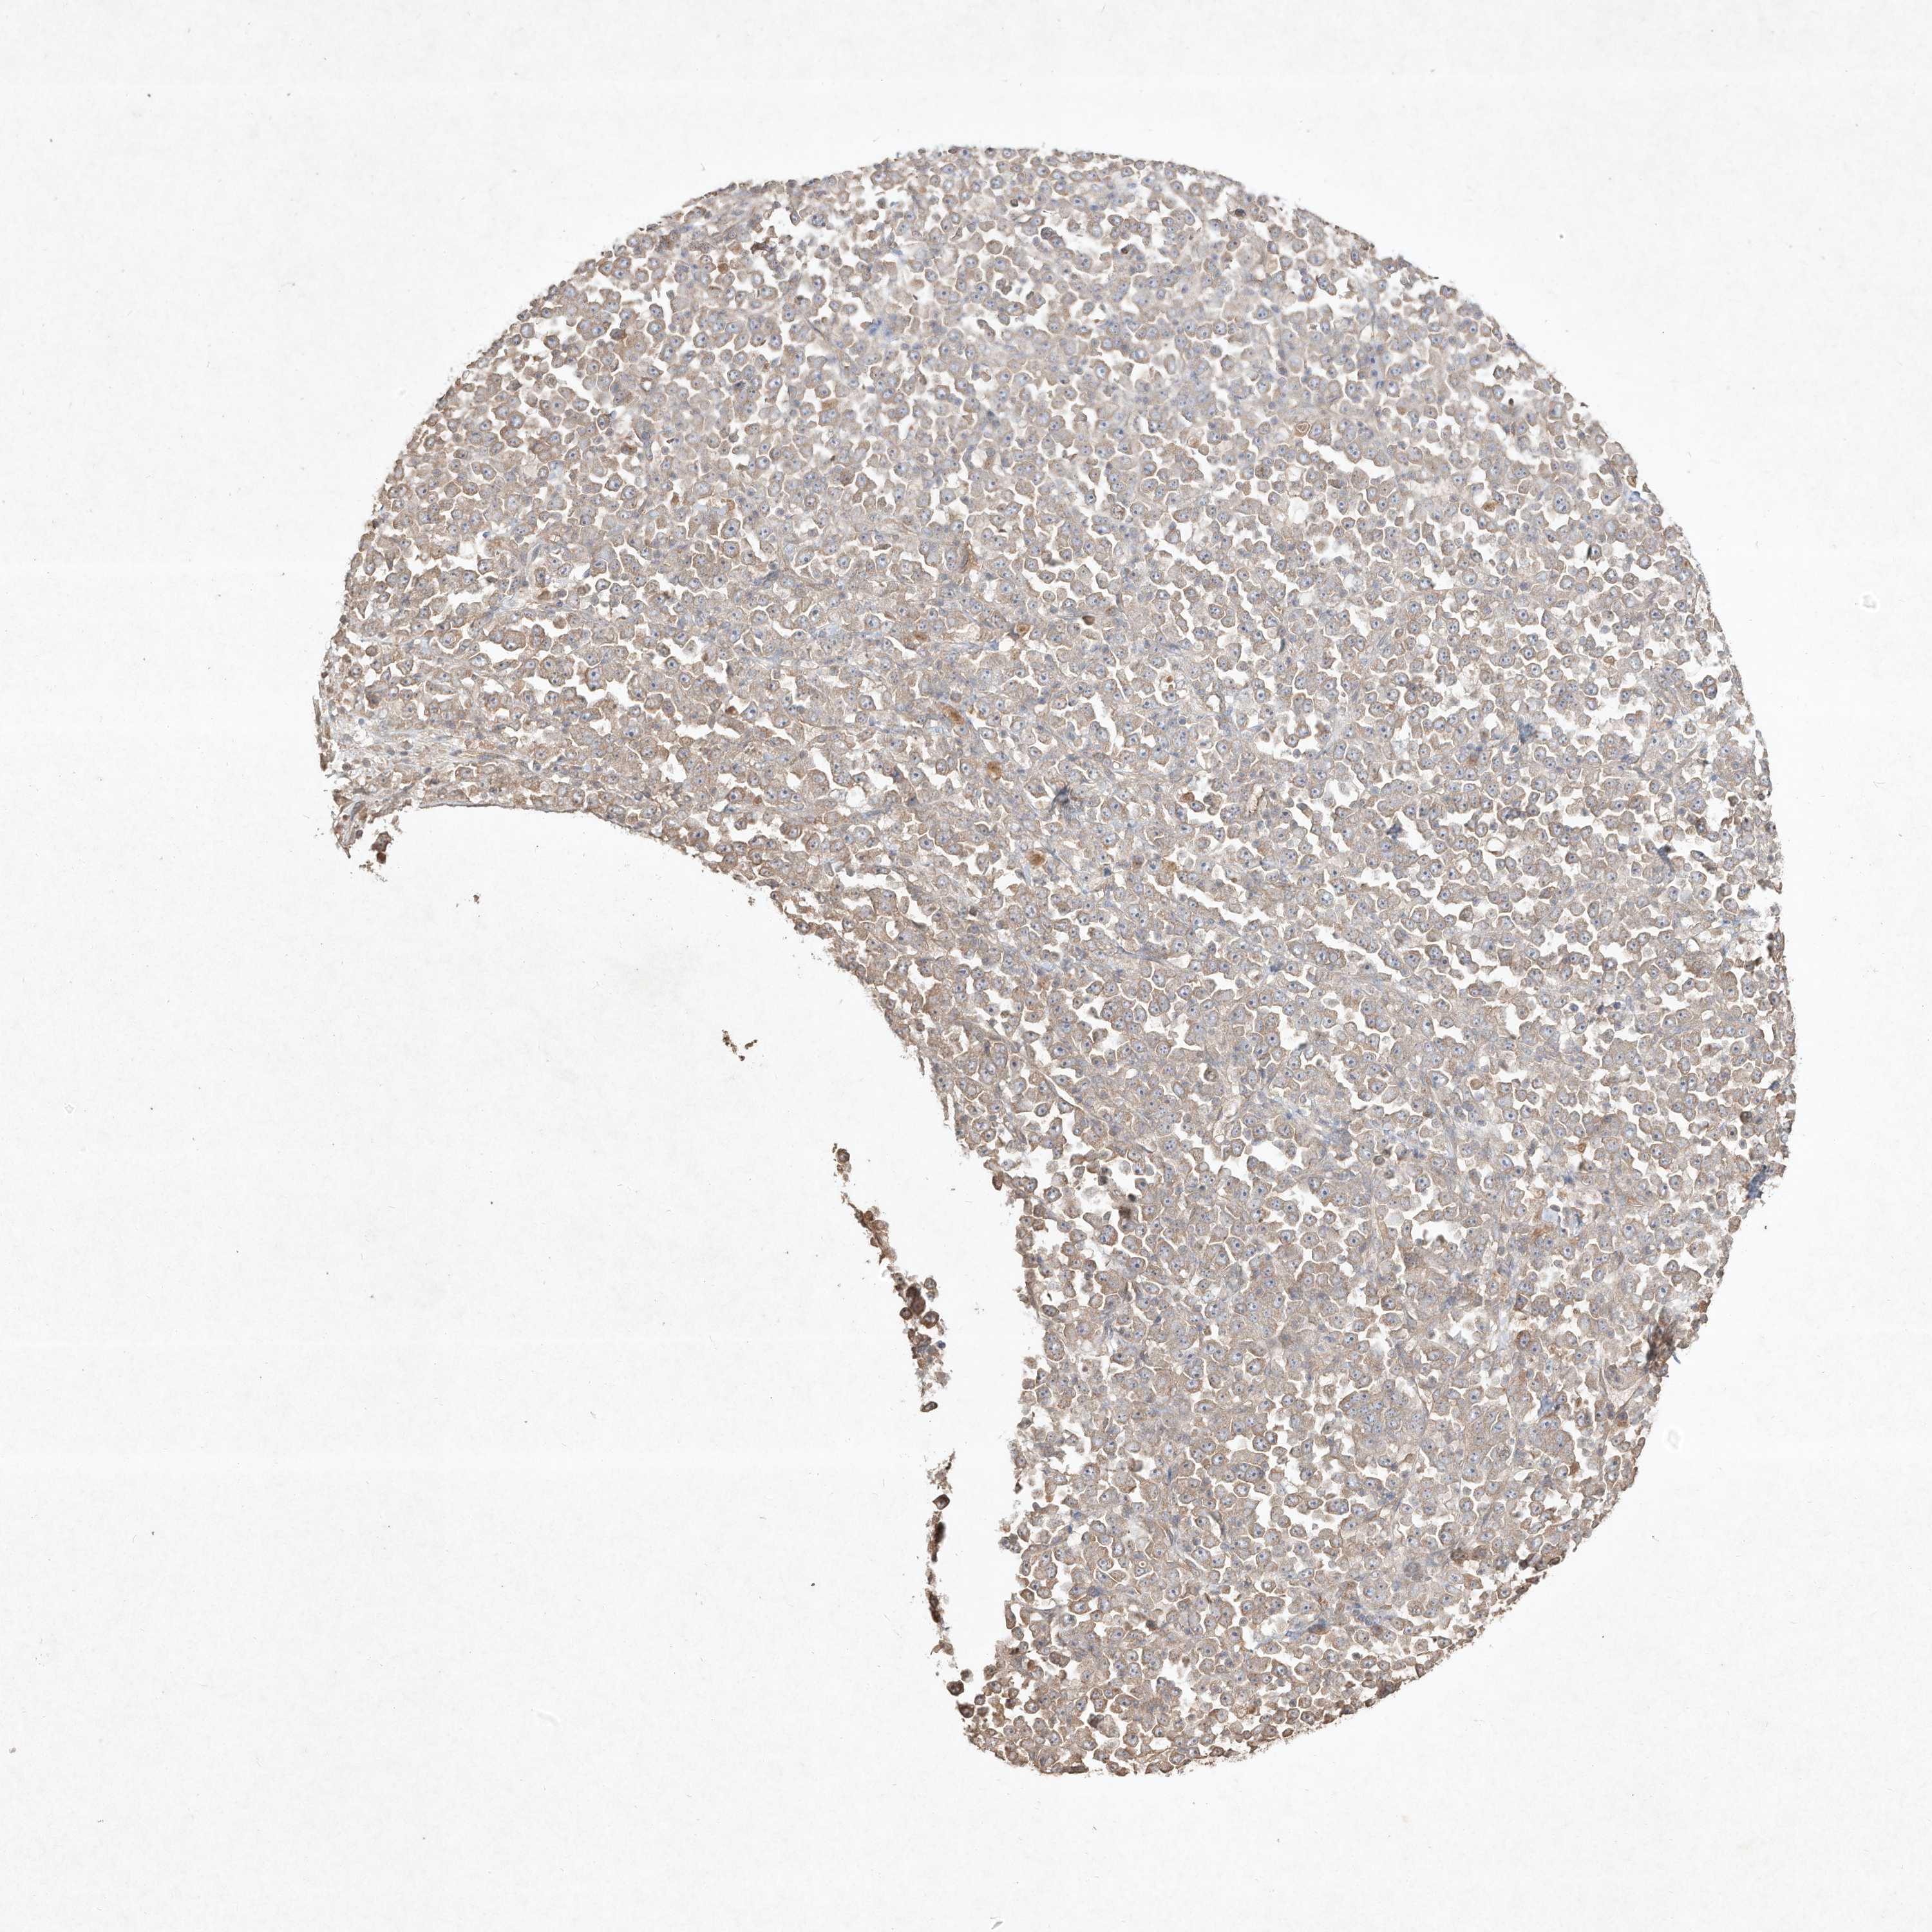

STOMACH CANCER - Protein expressioni

A mouse-over function shows sample information and annotation data. Click on an image to view it in a full screen mode. Samples can be filtered based on level of antibody staining by selecting one or several of the following categories: high, medium, low and not detected. The assay and annotation is described here.

Note that samples used for immunohistochemistry by the Human Protein Atlas do not correspond to samples in the TCGA dataset.

Antibody stainingi

Antibody staining in the annotated cell types in the current human tissue is reported as not detected, low, medium, or high, based on conventional immunohistochemistry profiling in selected tissues. This score is based on the combination of the staining intensity and fraction of stained cells.

Each image is clickable and will lead to virtual microscopy that enables deeper exploration of all samples and also displays staining intensity scores, fraction scores and subcellular localization as well as patient and tissue information for each sample.

Antibody HPA040619

Antibody HPA053987

Antibody CAB033836

Staining

Adenocarcinoma, NOS